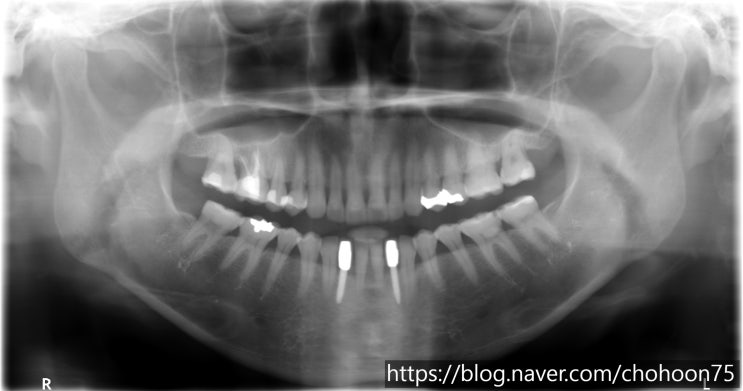

[조훈치과] 다수의 치아 상실 임플란트 치료로 대체

안녕하세요. 조훈 치과입니다. 많은 치아의 임플란트 식립이 필요하다면? 대부분의 치아를 상실하였을 때 ...